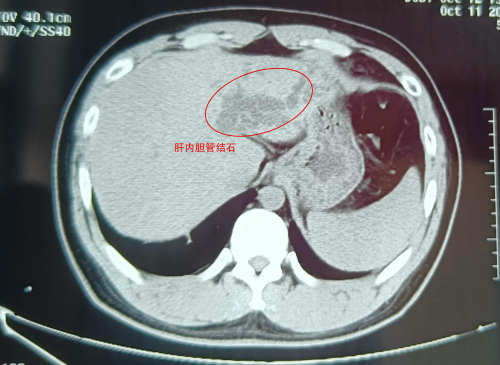

武漢的劉先生怎么也沒想到,看似普通的腹痛,竟險些讓自己丟了肝!近日,這位肝膽系統(tǒng)布滿結(jié)石的“小黃人”,緊急求助于武漢京都結(jié)石醫(yī)院。幸運的是,因為手術(shù)處理得當(dāng),劉···